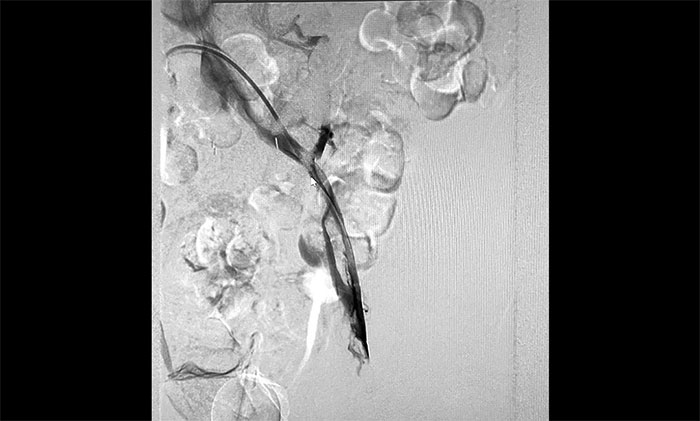

12月15日,席剛明教授在王貴平博士及介入團(tuán)隊(duì)協(xié)助下順利行將一個(gè)形似傘狀的人工濾器經(jīng)患者右側(cè)股靜脈穿刺迅速置入腎靜脈下方,“網(wǎng)”住了通往心血管和肺部的致命栓子,阻擋血液栓子進(jìn)入肺動(dòng)脈,及時(shí)挽救了患者生命。之后對(duì)病變血管進(jìn)行了血栓抽吸術(shù),及接觸性溶栓,抽出了大量血栓,復(fù)查下肢造影示血栓基本消失,下肢靜脈血管再通,整個(gè)手術(shù)順利完成。術(shù)后,患者下肢腫脹好轉(zhuǎn)。

▲ 下肢靜脈血管順利再通